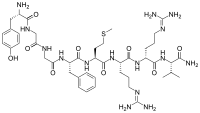

Opioid peptides

Dynorphins

Structures

| Dynorphins | ||||

|---|---|---|---|---|

Big dynorphin Big dynorphin |

Dynorphin A Dynorphin A |

Dynorphin B Dynorphin B | ||

Endomorphins

Endorphins

Structures

Enkephalins

Structures

| Enkephalins | ||||

|---|---|---|---|---|

DAMGO DAMGO |

||||

Propeptides

Others / unknown

- Adrenorphin